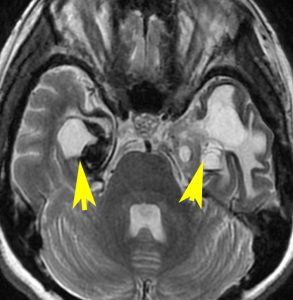

頭蓋底の脊索腫再発のために炭素イオン線 60グレイ16分割の治療を受けました。5年後に両側の側頭葉の脳壊死が生じました。そのために高度の高次脳機能障害となりました。両側の海馬(黄色い矢印)の壊死のために記憶が全くできません。でもしかし,この患者さんは重粒子線治療を受けなければ腫瘍再発で亡くなっていたと私は考えています

左内頸動脈が炭素線被爆したために閉塞しています。

重粒子線は高度の悪性腫瘍をやっつける強力な治療である反面,このように脳や動脈が被爆すればその組織も破壊されてしまいます。悪性腫瘍を破壊できる強力な粒子線治療は,その周囲の神経組織もかまわず破壊する治療であるとも言えます。